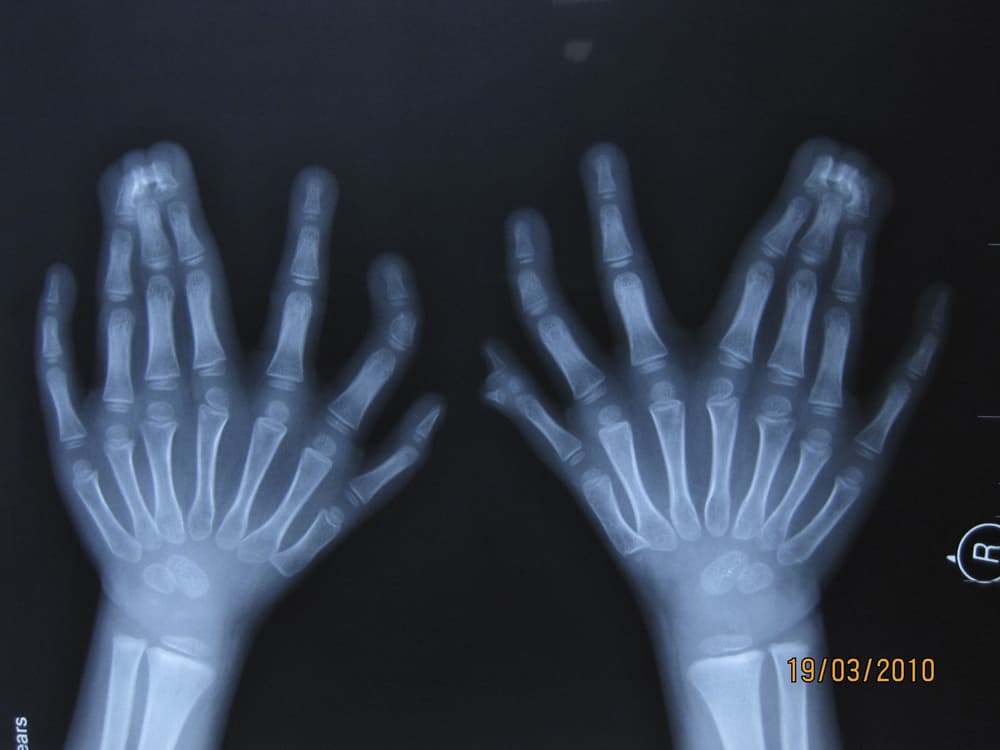

فتى صيني (6 أعوام) يظهر للإعلام أصابع يديه وقدميه -15 أصبع في اليد و 16 أصبع في القدم- داخل مستشفى شنيانغ الذي ستجرى بداخلة عملي